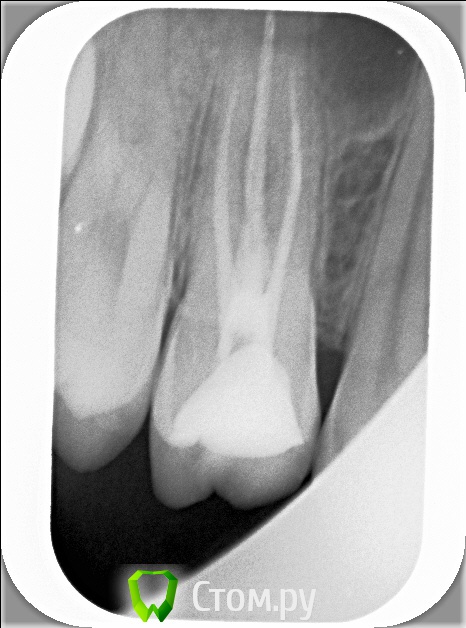

xSlon Опубликовано 13 августа, 2014 Поделиться Опубликовано 13 августа, 2014 Доброго времени суток!Прошу вашей помощи по сложному зубу, который не могут вылечить уже очень длительное время. Около 3х лет назад обнаружил, что при постукивании по 16му зубу(он был запломбирован совсем давно, не помню даже где и в каком году) появляется небольшая боль. Зуб не мешал, не доставлял беспокойств, но решив, что в таких случаях нужно действовать превентивно, пошел к стоматологу и рассказал о проблеме. Он посмотрел зуб(без вскрытия), сказал что никаких признаков боли не видит и считает что нужно удалять нерв. Поскольку зуб проблем не доставлял, я отказался.В течение этих трех лет состояние не ухудшалось, но я еще два раза ходил к разным стоматологам, описывал симптомы, они смотрели зуб, никаких признаков болезни не видели и советовали заниматься зубом когда он будет доставлять настоящие неудобства.В середине октября 2013 года ситуация ухудшилась, зуб начал периодически не сильно болеть, реагировать на холодное и горячее. В середине декабря ситуация сильно ухудшилась, зуб начал сильно болеть, сильно реагировать на холодное и горячее, сильно болеть даже при простом касании. Я обратился в стоматологию1 к врачу1, где мне вскрыли зуб, сказали что обнаружили под пломбой кариес, из-за кариеса произошло воспаление нервов и нужно удалять нервы в зубе. Боль была очень значительной, я не раздумывая согласился. Мне вскрыли зуб, поставили обезболивающее(или лекарство - точно не знаю), и сказали прийти через 7 дней, боль прошла. Через 7 дней мне обработали каналы и запломбировали Metapex'ом, сказали прийти в феврале(возможно еще удалили лекарство, точно не помню). В феврале мне за 1 посещение запломбировали постоянно каналы и за 2е посещение запломбировали зуб. К середине февраля лечение закончилось, жалоб не было. Единственное - удивляло что зуб, несмотря на удаление нервов, по старому реагирует на постукивание небольшой болью, но я не придал этому большого значения.Спустя 2 месяца, в середине апреля, остро заболел тот же самый зуб, с теми же симптомами - сильная боль, сильная реакция на холодное и горячее, сильная боль при касании. Врач1 был в отпуске, поэтому я пошел к Врачу2 в ту же самую Стоматологию1. Описал ситуацию, Врач2 посмотрела мою карточку, вскрыла зуб, осмотрела его, сказала что где-то должен быть 4й канал, но она не может его найти, сказала что вставила куда-то в зуб лекарство, сказала прийти через неделю.Боль утихла, пришел через неделю к тому же Врачу2, повторно вскрыли зуб, повторно поставили лекарство, но Врач2 сказала что 4го канала, который там должен быть, она не видит. Посоветовала обратиться к другому врачу, возможно, в другую стоматологию Через неделю, уже в начале мая, пришел повторно, запломбировали каналы Metapex'ом, поставили временную пломбу. По совету знакомых, в начале июня обратился к частному Врачу3, который специализируется на работе под микроскопом. Описал ей ситуацию, она вскрыла зуб, нашла четвертый канал, вставила туда лекарство, сказала прийти через неделю. Через неделю реакция зуба на слабые постукивания сохранилась, на приеме у Врача3 поставили более сильное лекарство(насколько я помню, с антибиотиком), прописала дополнительно в течении 5 дней пропить сильные антибиотики, сказала прийти через 10 дней. Через 10 дней, в конце июня, та же реакция зуба сохранилась. На приеме у Врача3 решили окончить лечение, потому как Врач3 на следующий день уходила в отпуск, а я, через несколько дней, уезжал в командировку. Перед отъездом пошел в Стоматологию1 к Врачу2, чтобы снять лекарство и временно запломбировать каналы и поставить временную пломбу. Врач2 сказала, что при вскрытии зуба она увидела 4й канал, попыталась определить длину канала с помощью прибора, используя самый тонкий инструмент(как я понял - это некая игла, подсоединенная к прибору, ее всовывают в канал, чем ближе кончик иглы к концу канала, тем сильнее он пищит), определить длину канала ей не удалось. Она предположила, что либо канал очень узкий, либо он изгибается, поэтому не удается дойти до конца канала.В командировке, в середине июля обновлял временную пломбу(от нее отвалился небольшой кусочек) в Стоматологии2, вкратце описал проблему Врачу4, он посоветовал использовать(дословно с листочка, который он мне дал) пломбировку материалом для к/к Forfenan Forident(резорцин-формалиновая паста). Сказал, что при таком методе, воспаленный нерв полностью обволакивается пастой, которая гермитизирует нерв, не давая разиваться воспалительному процессу. Сам воспаленный нерв остается, но организм, со временем, справляется с ним сам.Вернувшись из командировки, я пошел, по советам родственников, в Стоматологию3, к Врачу5. Описал ситуацию, сделал панорамный и прицельный снимки. Врач5, не вскрывая зуб, сказала что считает, что необходимо применить метод депофореза. Прошу вас, пожалуйста, посоветовать, каким образом вылечить этот зуб? Стоит ли попробовать резорцин-формалиновую пасту? Стоит ли делать метод депофореза? Возможно есть какие-то другие методы лечения? Прикладываю все снимки зуба из Стоматологии1Панорамный снимок из Стоматологии3, сделан 12 августа. https://yadi.sk/i/_hIqGP1IZaT4Y Ссылка на комментарий

xSlon Опубликовано 14 августа, 2014 Автор Поделиться Опубликовано 14 августа, 2014 Добавлен прицельный снимок 16го зуба от 12го августа. К сожалению, не нашел, как отредактировать первый пост. Ссылка на комментарий

Scrabble Опубликовано 31 августа, 2014 Поделиться Опубликовано 31 августа, 2014 Я вижу, что Вам запломбировали каналы термафилами-причём два носителя введены в дистальный, а не в мезиальный щёчный корень. В качестве силера(пасты) использовался форфенан? Если это так, то нужно всё распломбировать, полностью удалить форфенан-и ждать, пока стихнет симптоматика. Ссылка на комментарий